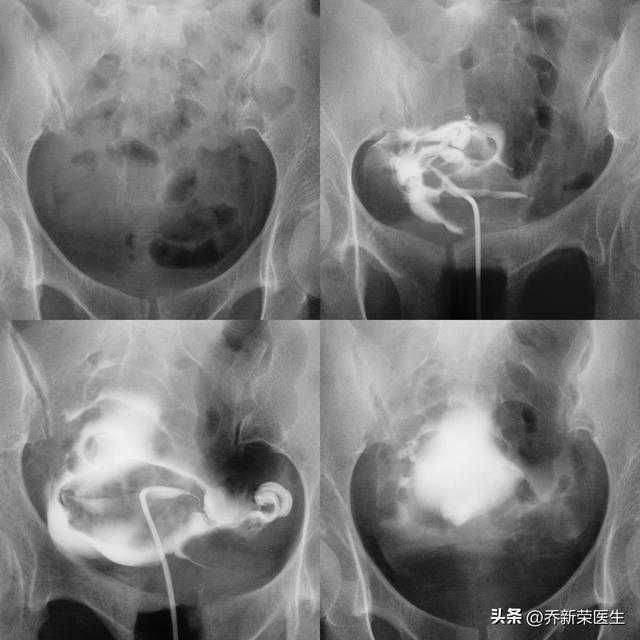

确实心理素质杠杠滴,十分钟后的结果来了

双侧输卵管通畅,病因考虑非特异性炎症,双侧输卵管拾卵能力由于堵塞时间较长较差,不过可以通过术后的中医中药、物理跟踪治疗恢复输卵管功能。